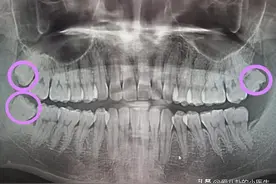

智齿又被称为第三磨牙,一般有1~4颗不等。由于生长空间有限,很多智齿无法正常萌出,它会歪着长、横着长,甚至野蛮生长……尽管它是人一生中最后长出的牙齿,牙医也建议尽早拔除。这四颗不能久留的牙齿,可以一次性拔了吗?《生命时报》采访专家,分析什么样的智齿需要拔除,给拔智齿列张注意清单。

红网时刻新闻3月21日讯(通讯员 赵娅涛)世界上有一种疼叫智齿疼。智齿问题,一直受到小伙伴们的关注,因为它常常让人“痛不欲生”!此时大家脑海里的第一反映可能就是“拔智齿”,那么智齿到底要不要拔?今天,长沙口腔医院的医生就带大家来了解一下。